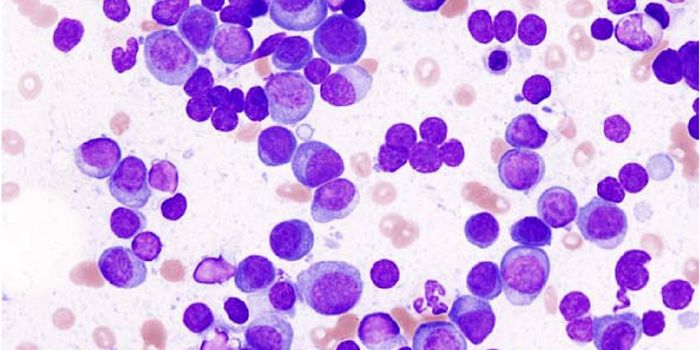

MAR 29, 2022Clinical & Molecular DXMyelodysplastic syndromes (MDS) describe cancers resulting from abnormal cells in the bone marrow. The abnormal bone mar ...

MAY 01, 2018CancerResearchers have developed a microfluidic device that can detect circulating plasma cells in whole blood; therefore, neg ...